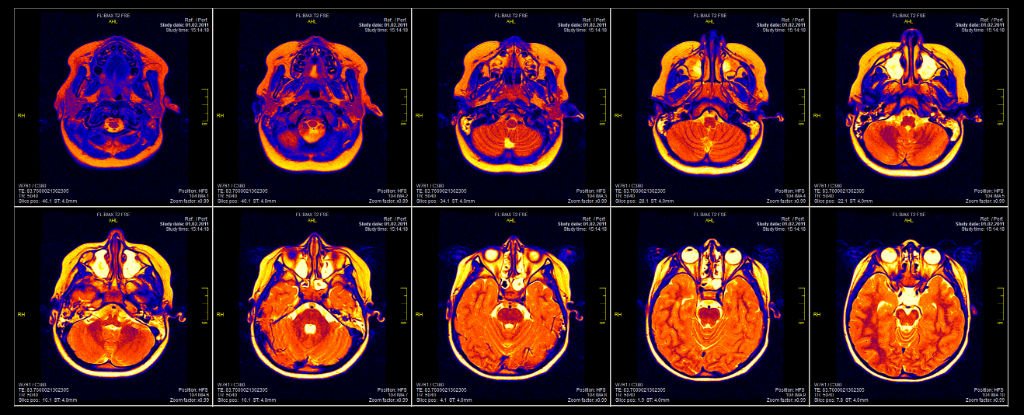

Some news I thought some of you may also find interesting...a friend is helping fund an upcoming IV DMT brain imaging study being conducted by Imperial College London. His friend is the PhD student spearheading it, under the supervision of Dr Robin Carhart-Harris and Professor David Nutt. The study will be investigating the effects of different dosages of DMT on the brain via EEG and fMRI. I'm signed up for the pilot study...two study days, a week apart, in November. On one day I will receive the placebo (IV saline), the other I will receive my allocated dose of IV DMT, and obviously I don't know which order I shall receive them.